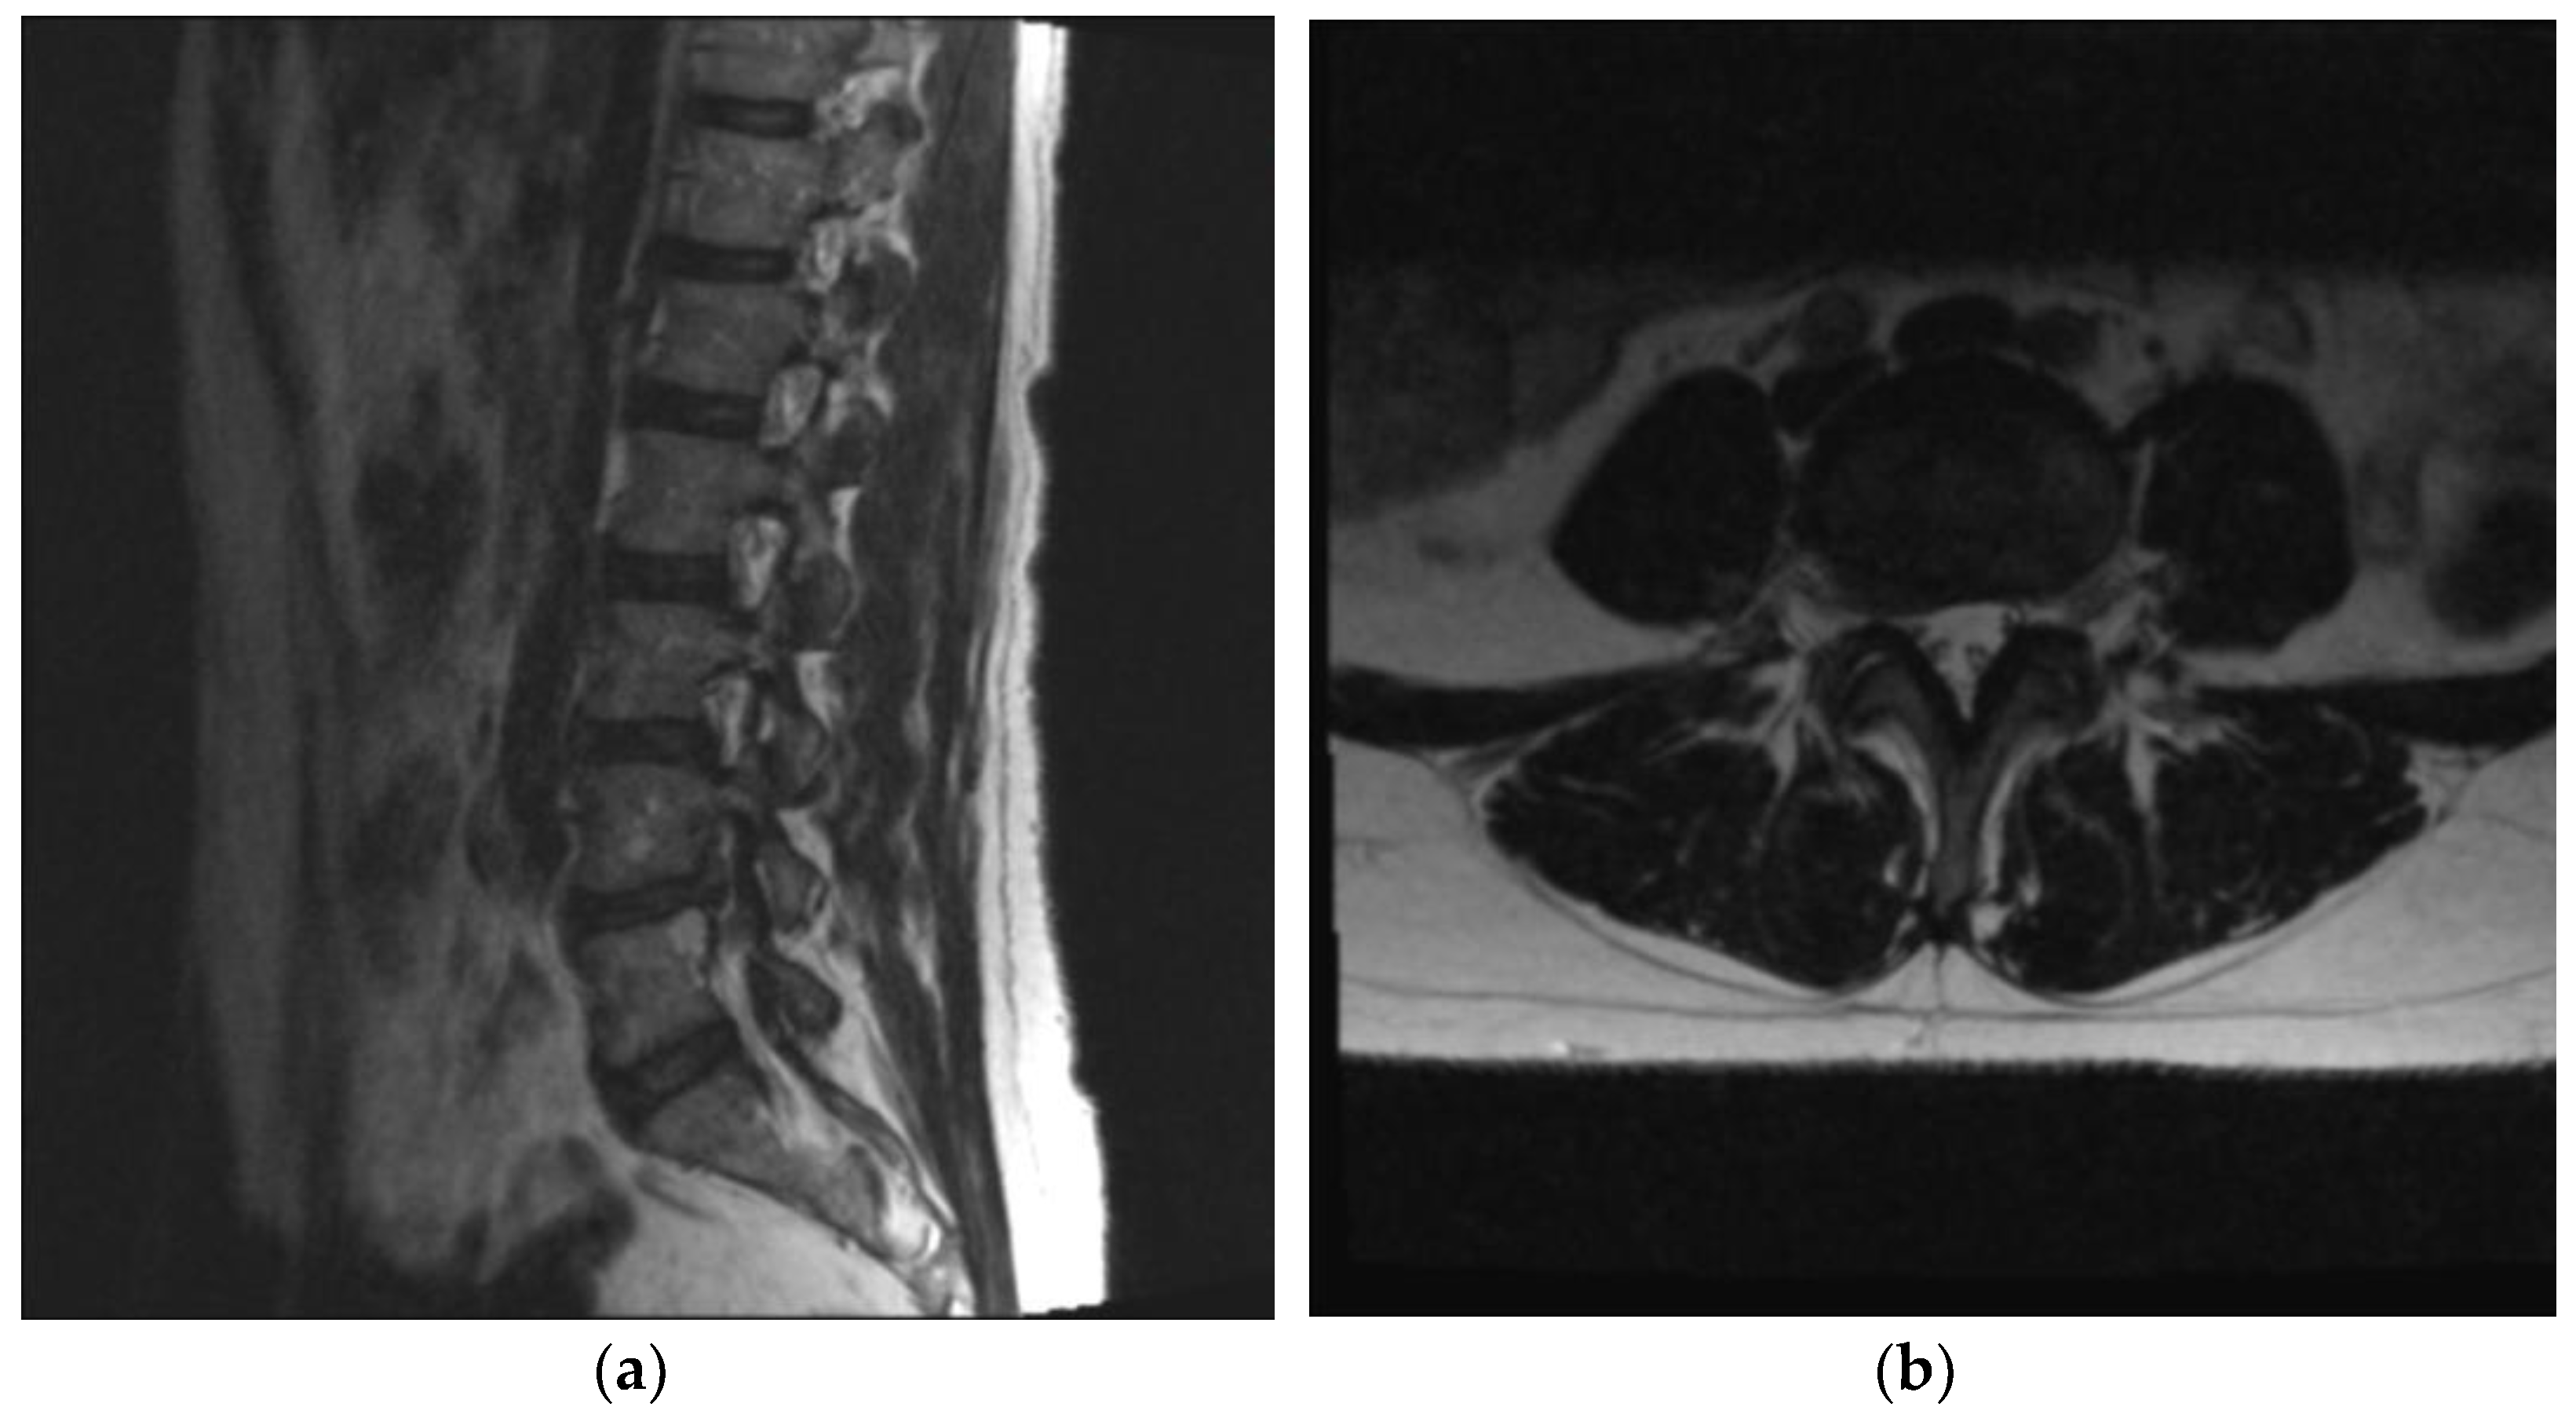

2.2. Technical Description